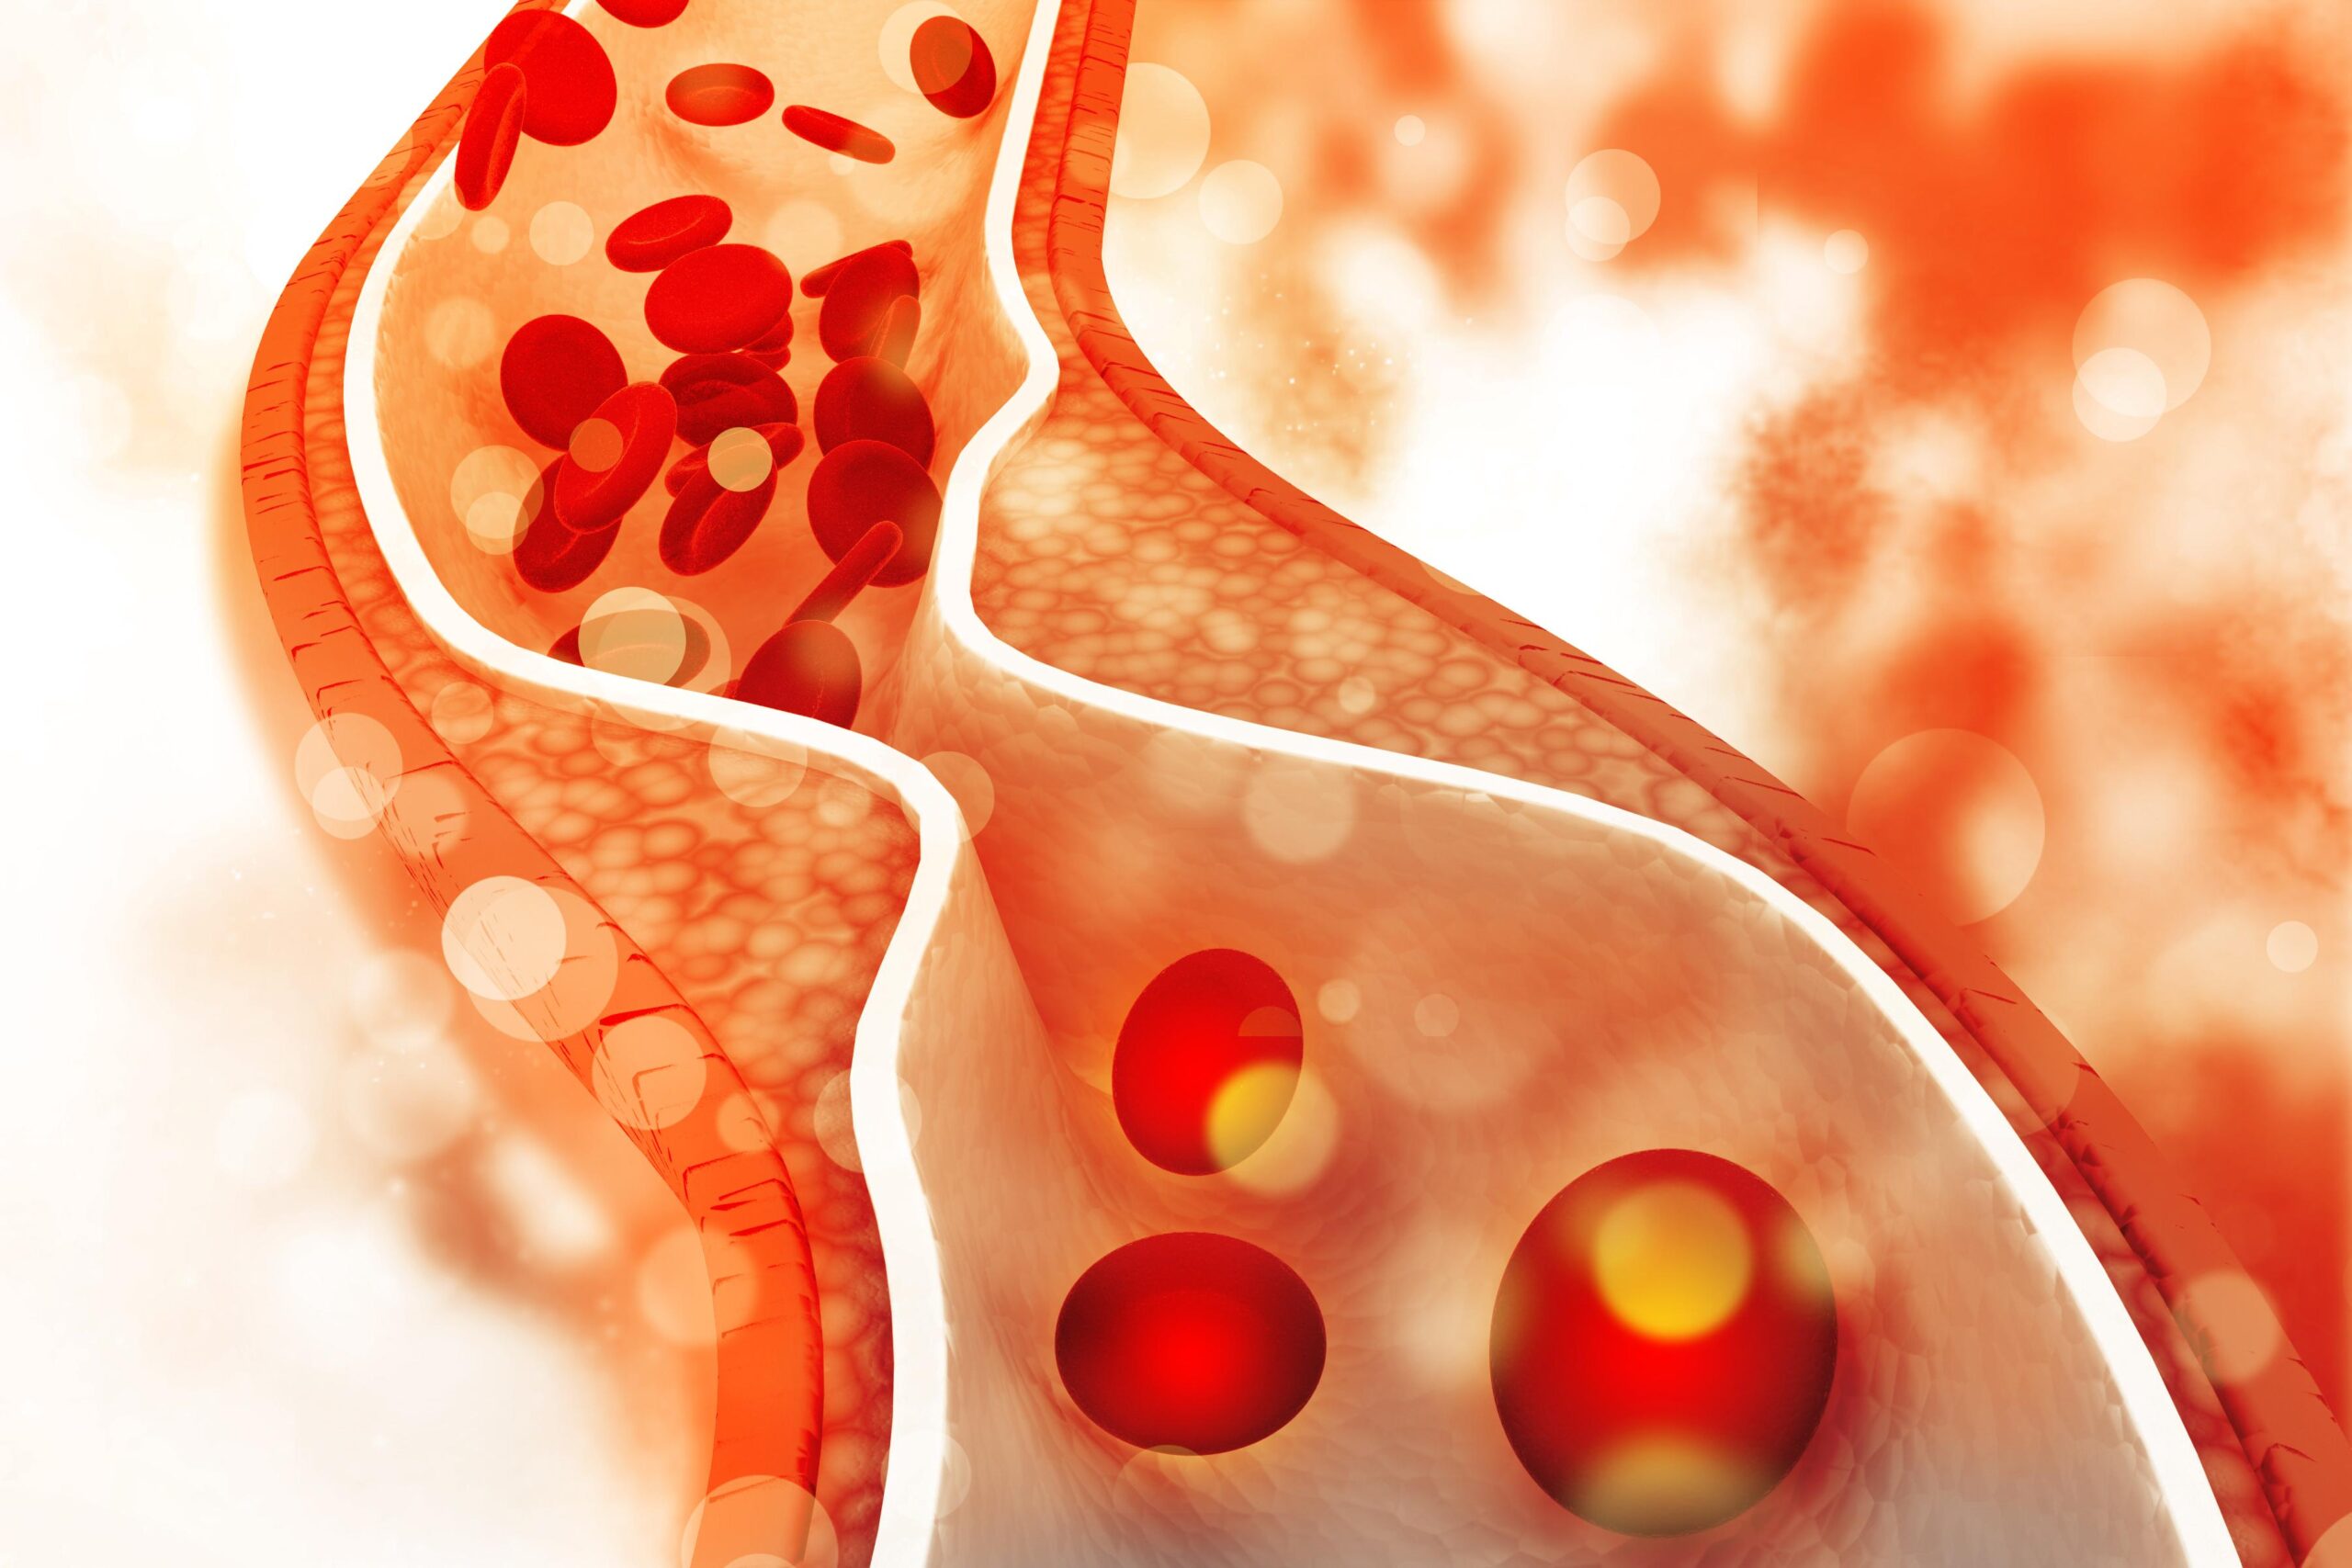

داروهایی برای درمان هایپرکلسترولمی خانوادگی : هایپرکلسترولمی خانوادگی یک بیماری ارثی است که باعث کلسترول بالا میشود. به مبتلایان به این بیماری معمولاً استاتینها، ازتیمایب و داروهای اضافی برای کاهش موثر کلسترول تجویز میشود.

داروهایی برای درمان هایپرکلسترولمی خانوادگی : اسیدهای چرب امگا ۳ با دوز تجویزی میتوانند برای درمان تری گلیسیرید خون بسیار بالا (بالای ۵۰۰ میلیلیتر در دسیلیتر) استفاده شوند. اسیدهای چرب امگا ۳ همچنین به عنوان مکمل در دوزهای پایینتر موجود هستند.